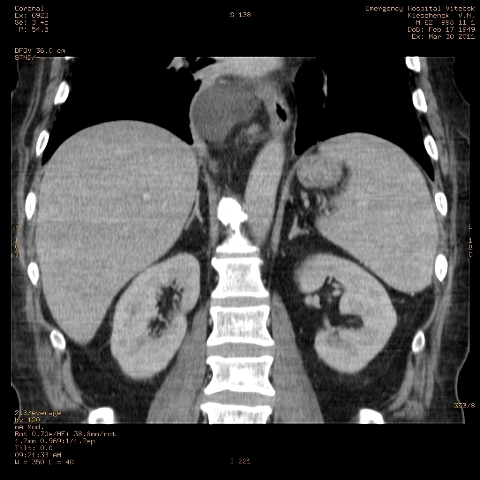

при исследовании органов брюшной полости по поводу абсцесса печени, в нижнем этаже средостения выявлено образование неоднородной плотности (-5-+25), при в/в контрастировании - не контрастируется, при per os - затёков из пищевода нет, неправильно овальной формы. предположительно киста перикарда? спасибо за помощь!

Может быть enteric duplication cyst. Как бы есть грыжа жира hiatal. И что с печенью? Мало срезов.